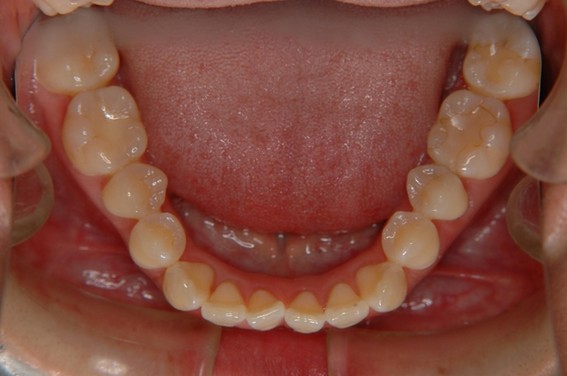

| 主訴 | 前歯が逆に噛んでいるところがある。歯のがたつき。 |

| 治療内容 | 表側ワイヤー矯正、4本抜歯を行いました。 |

| 治療費 | 880,000円+ダイレクトボンディング33,000円(税込) |

| 治療期間 | 30ヶ月 |

| 治療回数 | 30回 |

| 想定されたリスク | 歯根吸収、歯髄壊死、歯髄充血、歯肉退縮のリスクがありました。 |